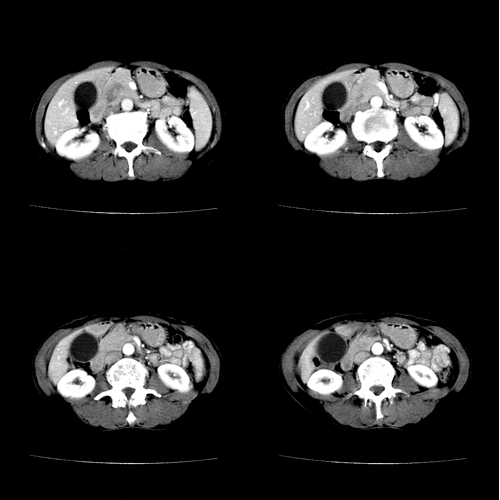

患者 女 60岁,曾多年胆结石及胆管结石,今行ct复查,非常经典.现上传,请讨论.

典型的胆总管铸型结石。

支持胆总管结石。胆囊增大受压,肝内胆管及胰腺管无明显扩张。很有意思的病例,能有冠、矢状重建图像观察就更好了。

相当漂亮的“总胆管(铸型)结石”。多谢楼主!

结石这么大,肝内胆管扩张不明显,胆囊扩张明显。能否考虑结石位于胆囊管内并外压总肝管?

胆总管内多层同心圆样结石,确属精典,谢谢卜一老师!

肝内胆管扩张形态也支持胆总管结石的表现

蛔虫性结石